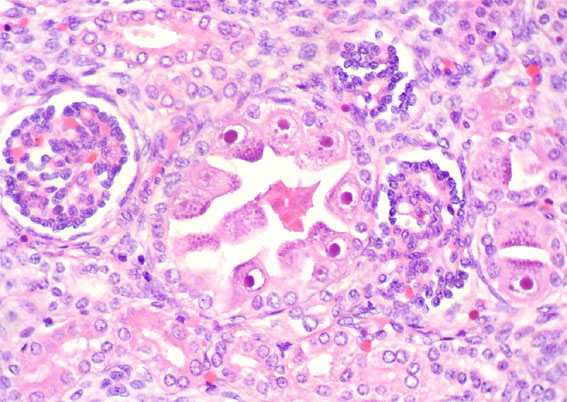

En ambos riñones fetales se observa lo mostrado en las siguientes imágenes.

Figura 1.

H&E, X100.